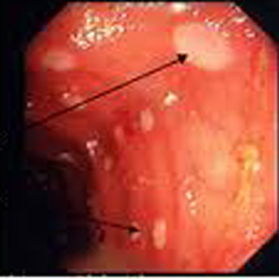

Aspect endocopique du

maladie de Crohn au stade precose est image ulceration

aphtoide de ileon et image de lesions nodulaires du colon

Aspect macroscopique du lesions nodulaires

du colon du maladie de Crohn . Image endoscopie du

colon . |

Lesions

d'ulceration aphtoide precoce du colon transverse et

colon sigmoide du maladie de Crohn : Image

fibroscopie du colon . |